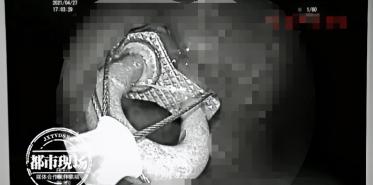

为了尽量减少对身体的伤害,医生决定通过内镜来取出,仅耗时7分钟左右,医生就成功将这把金属锁取出。